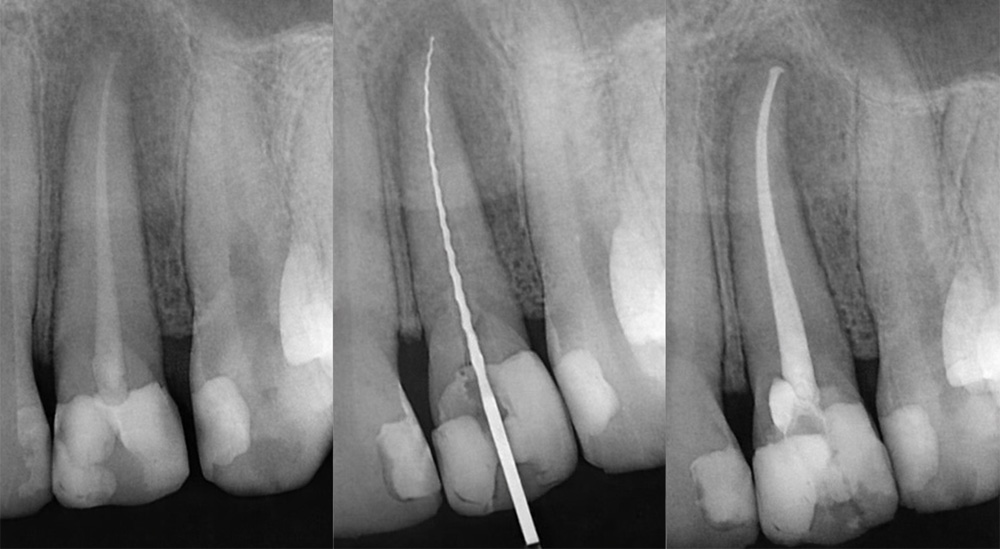

Las principales fases del tratamiento endodóntico convencional son:

• La conformación del conducto.

• La desinfección del sistema radicular.

• La obturación tridimensional del sistema de conductos.

Un correcto diagnóstico y planificación del tratamiento se realiza tras una evaluación clínica exhaustiva, complementada con radiografías.

• Conformación y desinfección del conducto radicular mediante técnicas mecánicas y químicas.

• Obturación tridimensional con materiales biocompatibles y sellado adecuado.